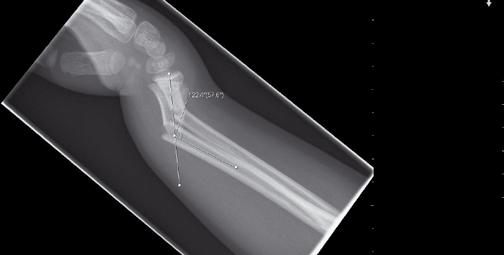

På onsdagsmorgonen gick Yngvar Krukhaug, Bergen, på ett didaktiskt sätt igenom eviden sen för olika behandlingsstrategier av distala radiusfrakturer. ”Take home message” blev att de data vi grundar våra beslut på generellt är av undermålig kvalité, att gipsbehandling kan användas i 80 % av fallen och att det nu finns evidens för användning av volar plattfixation vid instabila AO C1 och C2 frakturer. Vid mer splittrade frakturer finns inga data som visar att volar platta är bättre än externfixation, nå got som ytterligare diskuterades vid efterföl jande symposium om indikationer för vinkel stabila plattor med Ingvar Allvin, Örebro, som moderator.

Ortopedtraumatologiska sällskapet och Svens ka skulder- och armbågssällskapet med mo derator Per-Olof Josefsson, Malmö, fortsatte med en grundlig genomgång av behandlings strategier vid traumatiska armbågsskador. Lars Adolfsson, Lindköping, underströk i sitt anförande att distala humerusfrakturer hos vuxna ofta är svårbehandlade och bör skötas av få individer som kan skaffa sig erfarenhet av frakturtypen. Frakturer bör handläggas dag tid och inte i blodtomt fält då operationerna ofta tar lång tid. Rekommendationen blev att använda två parallella plattor, en på medialoch en på lateralsidan av distala humerus, då denna teknik bättre fångar och fixerar splittra de fragment än vinkelrätt anbringade plattor. ”Triceps split” rekommenderades som frilägg ningsteknik medan olecranonosteotomi oftast bör undvikas.